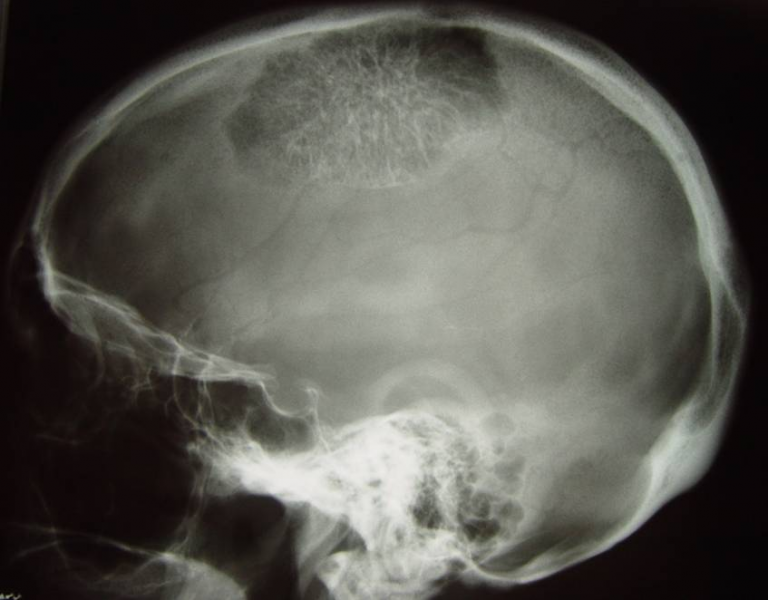

El siguiente caso es un hemangioma cavernoso craneal que se expande hacia el interior de la cavidad presionando el cerebro.

RM T1 y T2 respectivamente.

Impresionante imagen de la cirugia para extirpar el hemangioma. Se ve claramente como se expande hacia el interior de la boveda craneal y levemente por el exterior. En su textura pueden apreciarse los capilares recorriendo toda su superficie.